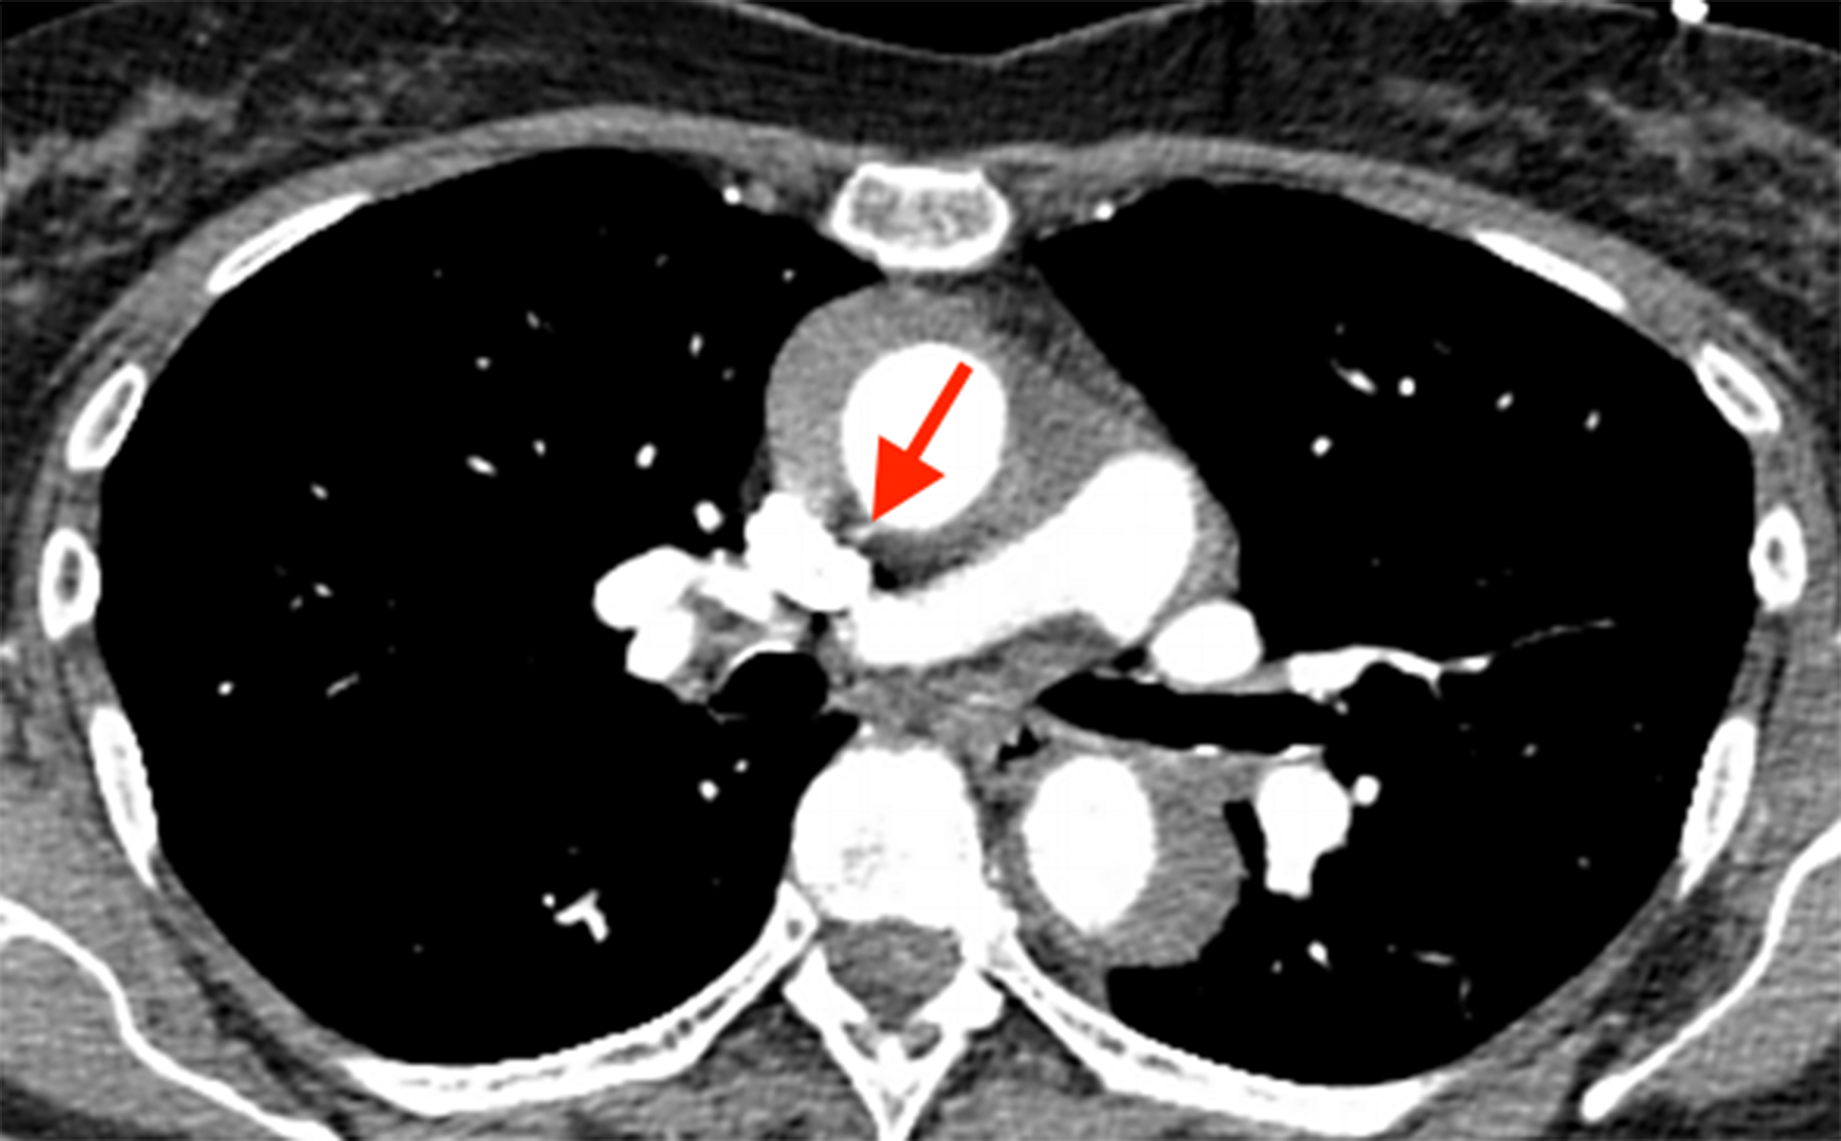

Dr. Morad Sallam, clinical lead and head of service at Guy’s and St. Thomas’ NHS Trust, London, UK, and an honorary senior lecturer at King’s College of London, London, UK, presented on “Aortic Infections Lessons Learned from 100 AGI.” He covered topics such as open or endograft aortic infections, infective aortitis (mycotic aneurysms/ pseudoaneurysms), the pathways for mycotic aneurysm and graft infections, and multiple case studies.